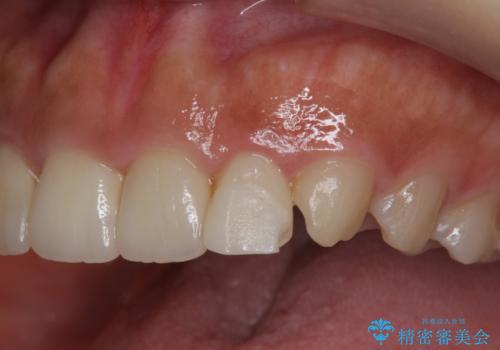

欠けた前歯を綺麗にしたい

- 「欠けてしまった前歯のコンポジットレジン修復をくり返していたが、すぐ外れてしまい困っている。」

、と前歯の欠けの改善を求めて来院されました。

噛み合わせが深く、前歯の突き上げが大きいため欠けの繰り返しを防ぐべくセラミッククラウンによる補綴を行うこととしました。

審美性の改善を達成することができました。